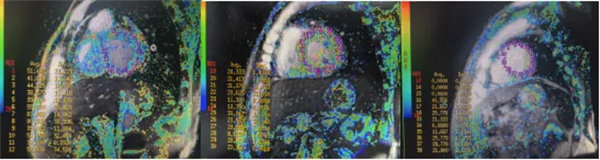

在常規心臟MRI檢查中,醫學影像科發現患者心肌異常表現,考慮鐵過載性心肌病,為明確診斷要進一步加做鐵定量技術,加掃T2 mapping序列。CMR鐵定量技術是目前評估心肌鐵含量的“金標準”,能夠快速、無創、精準量化心肌內鐵沉積程度,檢查結果提示患者局部心肌T2*值顯著低于正常范圍,符合鐵過載性心肌病的診斷標準。

CMR是目前唯一能定量檢測組織鐵負荷的無創影像學手段,主要依賴其 T2*mapping技術測量的T2*弛豫時間(T2*值)間接量化組織鐵含量。當CMR檢測出心肌T2*<20 ms時,初步診斷心肌鐵過載,T2*值<10-15ms時,提示心功能受損風險顯著增加。T2值越低,鐵沉積越嚴重。目前T2*mapping技術檢測T2*已作為臨床診斷肝臟、心肌鐵過載的首選無創檢查,也被用作隨訪工具評估疾病進展和療效。

基底部、中間部及心尖部 局部心肌T2*值明顯減低T2* 10-20/s, 部分小于10/s

心肌信號局部減低 呈現“黑色心肌”表現,這是由于鐵沉積導致局部磁場不均勻,引起信號丟失(失相位)。

肝臟和脾臟信號改變 矢狀位梯度回波定位圖像可顯示肝臟和脾臟信號降低,提示肝脾鐵沉積,T2*>6.3及R2*>160/s表現中度鐵過載。